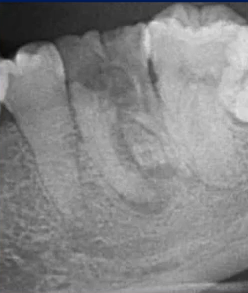

【病例4】

29岁,女性,自感牙体不适来院就诊

主要诊断:牙体——47龋坏伴根尖炎

牙列——35、45牙缺失,乳牙滞留,38、48智齿埋伏阻生

根尖片进一步诊断

47龋坏伴根尖炎

曲面断层片怎么看口腔精读 | 一次性教你看懂曲面断层片!_https://www.jmylbn.com_新闻资讯_第54张

曲面断层片怎么看口腔精读 | 一次性教你看懂曲面断层片!_https://www.jmylbn.com_新闻资讯_第55张

37继发龋!根尖炎?